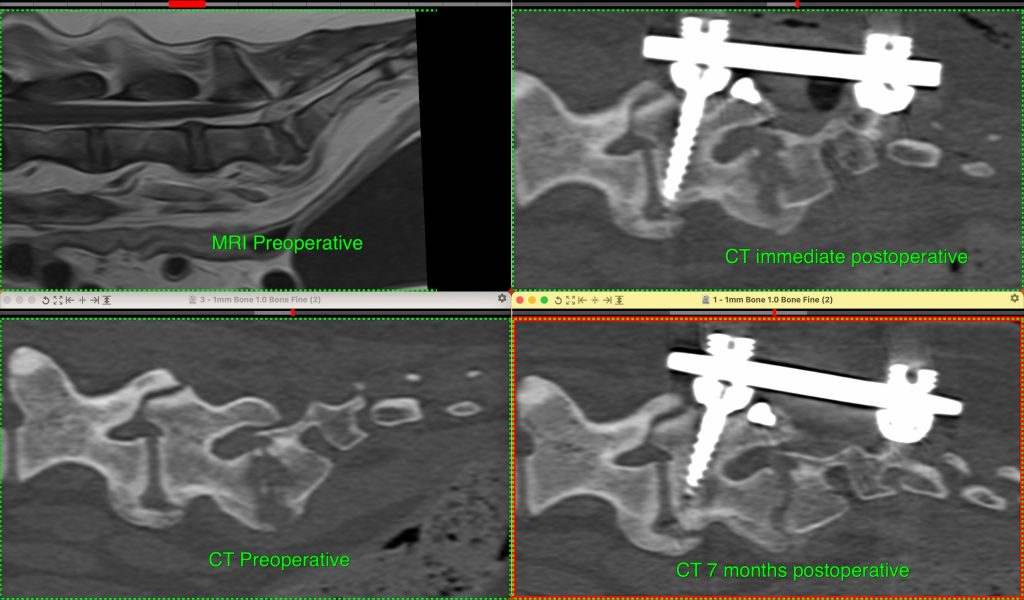

Dr Leblond performed a long but successful surgery on Teebo by placing pedicle screws and rods to stabilise his lumbosacral spine as well as antibiotic sponges to help fight infection.

“In some patients, we have even been able to follow-up the viability of the implants using CT images for several months and demonstrate that the infected bone was growing back filling up the previously infected gap.”